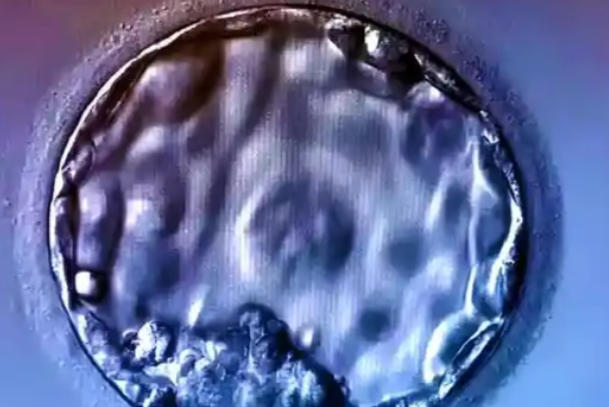

4cc囊胚作为囊胚分级体系中质量中等偏下的等级,常常引发备孕家庭的深切担忧——"4cc囊胚生出的小孩健康么"这个问题的背后,蕴含着对未来子代健康的深切关注。根据国际囊胚分级标准,4cc囊胚指的是处于扩张期,但内细胞团和滋养层细胞评级均为c级的囊胚,这意味着其在细胞数量和排列结构上都存在一定不足。本文将系统解析4cc囊胚的发育潜能、健康风险及相关临床数据,为面临此类情况的患者提供科学、客观的参考依据。

Gardner囊胚评分系统主要从囊胚扩张程度、内细胞团和滋养层细胞三个维度进行评估,其中内细胞团发育为胎儿本体,滋养层细胞则形成胎盘等附属组织。4cc囊胚虽然完成了囊胚腔扩张,但其内细胞团细胞数量少、排列松散,滋养层细胞也呈现稀疏状态,这些形态学特征确实反映了胚胎发育潜能的相对不足。